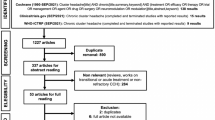

This study consisted of a randomized, double-blind, crossover design with two 1-month periods separated by a 1-week wash-out period and an extension 10-month open phase (Fig. 1). The trial was conducted in four academic centers in accordance with the Declaration of Helsinki, and was approved by the ethics committee of the Nice University Hospital (Comité de Protection des Personnes Sud Méditerranée V). All centers associated a neurological team belonging to the “Observatoire des Migraines et Céphalées” set up by the French Headache Society [15] and a neurosurgical team highly qualified in the DBS domain and pain management.

Design of the study. The randomized phase of the study included two 1-month treatment periods (week 8 to week 12 and week 13 to week 17) separated by a 1-week washout period. Patients were evaluated at inclusion, 1 week before surgery; 4 weeks after surgery (before active or sham stimulation) and at the end of the first randomization period (weeks 12 and 17). This randomized phase was followed by a 10-month open phase. Patients were evaluated at the end of this phase (week 52)